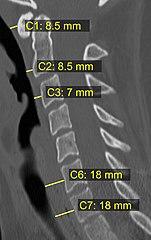

CT scan or X-ray images are evaluated for the presence or absence of directly visible fractures. In addition, indirect signs of injury by the vertebral column are incongruities of the vertebral lines,[11] and/or increased thickness of the prevertebral space:[12]